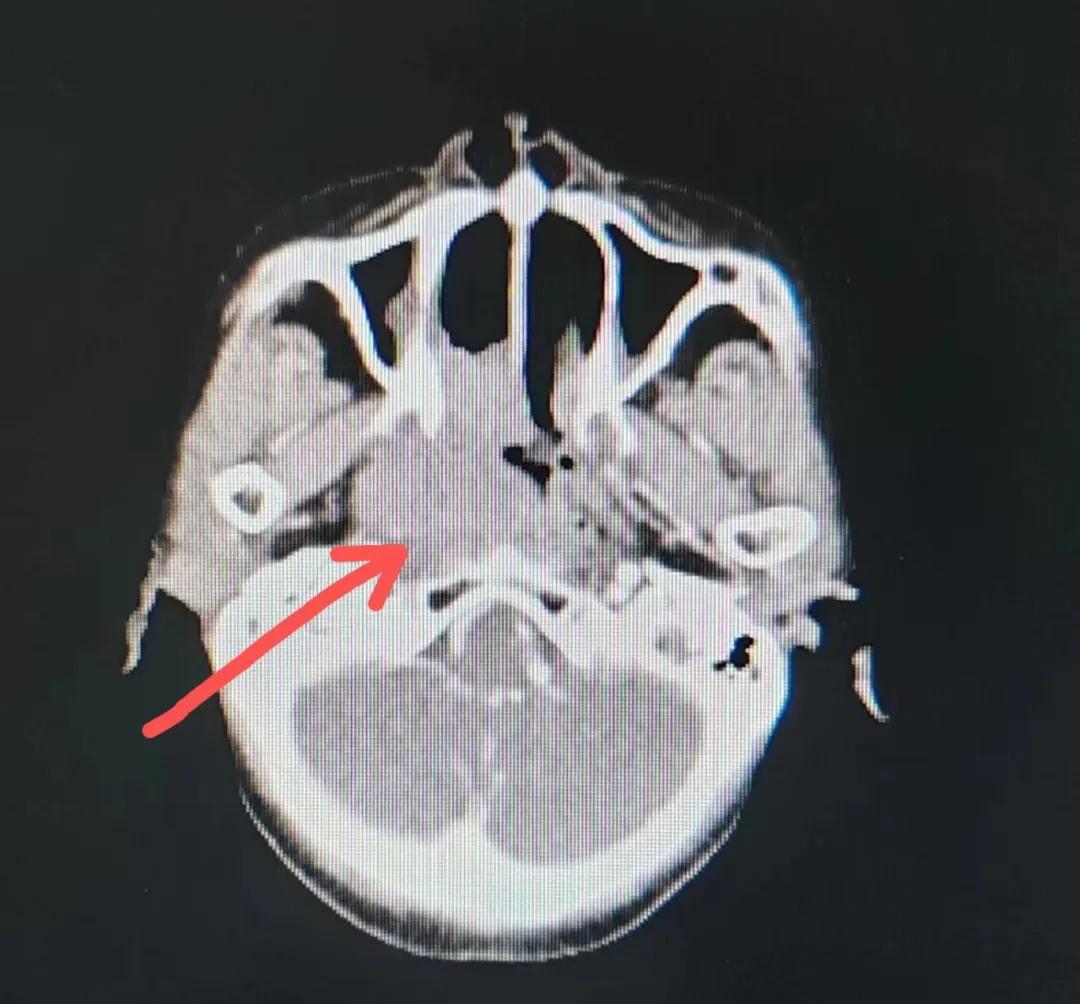

70歲的彭阿姨,5個月前因鼻部瘙癢伴流血不止在當地診所治療,瘙癢和出血癥狀不但沒有得到有效控制,反而進行性加重,并出現(xiàn)鼻腔堵塞、進食困難,經外院病理活檢確診為“鼻腔惡性淋巴瘤”。不斷加重的病痛已嚴重影響了老人的生活質量,為求診治,患者及家屬于今年2月份慕名來到了市二院放療科。

治療前

老人因鼻部腫物堵塞鼻腔并且侵犯鼻咽導致鼻塞、疼痛、吞咽困難,身心都備受煎熬,趙亮主任在詢問其病史期間幾度落淚。趙亮主任向患者及家屬解釋說:“現(xiàn)代放療比過去的傳統(tǒng)放療設備先進,技術不斷提升,能對腫瘤區(qū)域的照射劑量進行優(yōu)化,做到準確定位、精準照射,同時,最大限度地降低正常組織的受量,對全身情況影響很小。”

考慮到患者年齡較大、體質差,手術難度大,且常規(guī)的放射治療難以保護患者晶體造成患者雙眼視力損傷,放療團隊以最快的速度制定了精準放射治療方案并開始為其實施治療。僅僅數日后,老人腫塊出血即得到控制,腫塊明顯縮小,放療20次后腫塊迅速縮??!

治療后

放療結束,除了放療處的皮膚輕微放射性皮炎外,基本沒有什么不良反應。復查發(fā)現(xiàn),鼻腔淋巴瘤已不可見,目前患者已康復出院。